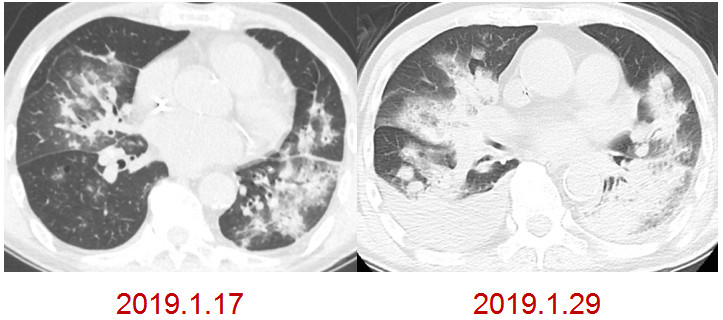

男性,85岁,发热、气短。1月17号表现为两肺斑片状实变影,经过一轮治疗,效果欠佳,病情继续进展,两肺比较对称,没有心衰,也没有水肿的改变。最终诊断是重症肺炎,调整碳青霉烯类药物的治疗后有所好转。